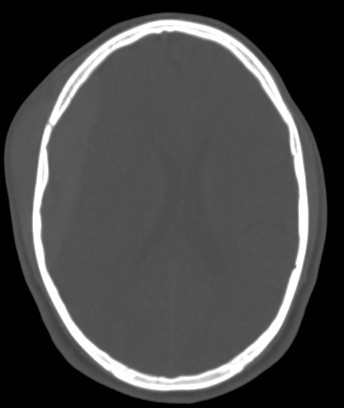

• associated right fronto parital fracture seen

• Biconvex (lentiform) hyperdense collection adjacent to the inner table of the skull.

• Underlying skull fracture commonly visible, especially in the temporal region.

• Associated fractures or pneumocephalus.